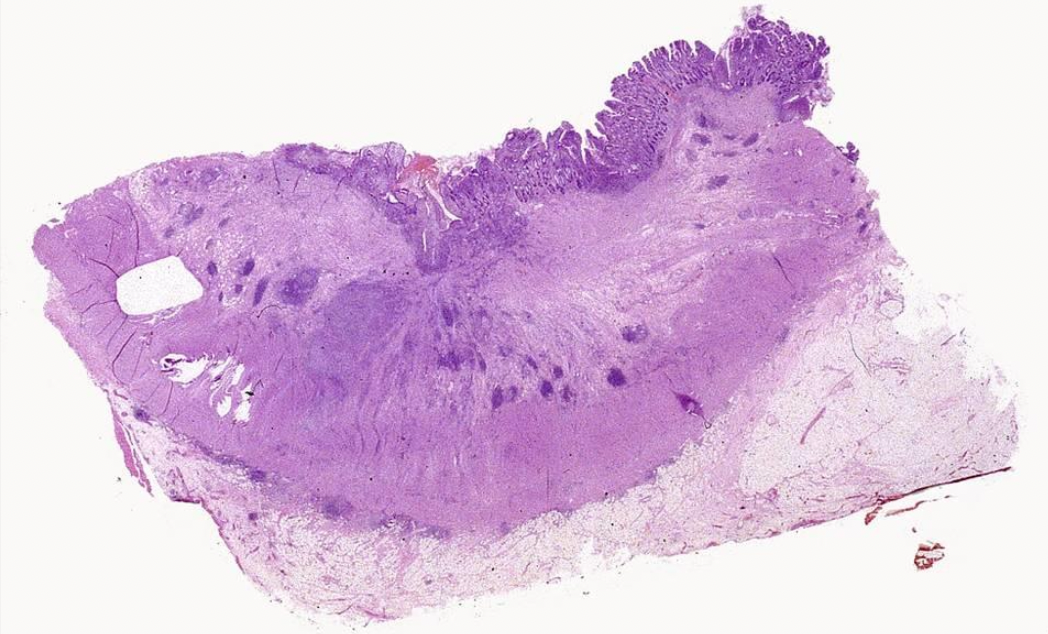

Colon Cancer